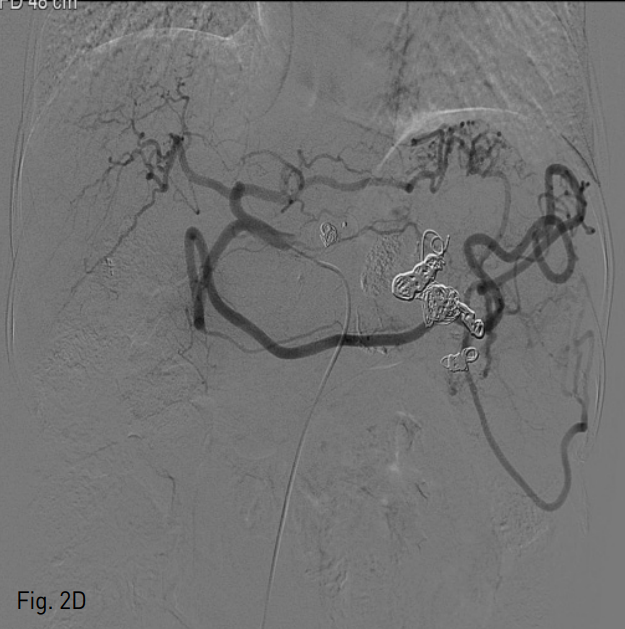

Fig. 2

A. Initial splenic arteriogram shows a large splenic artery aneurysm in proximal portion of splenic artery.

B. Post embolization angiogram shows faint visualization of largest splenic artery aneurysm on delayed phase.

C. Right gastroepiploic angiogram shows multiple fine feeders to largest splenic artery aneurysm.

D. Final celiac angiogram shows complete exclusion of splenic artery aneurysm and prominent splenic collateral pathways such as perigastric and gastroepiploic anastomosis.